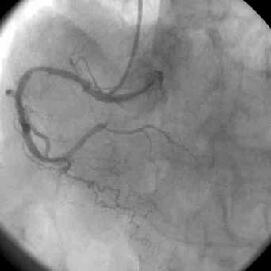

PCI前

PCI後

○○です

○○先生の症例についての追加ですが

○○先生の症例の写真を添付しておきます。

ちなみにJR4で、パラレルワイヤーを使用してステントを

閉塞部位と、その末梢の2箇所に留置しました

TRIをはじめて今までALのお世話になることもなく、JR4, IR1.5

、パラレルワイヤーでなんとか成功しています。